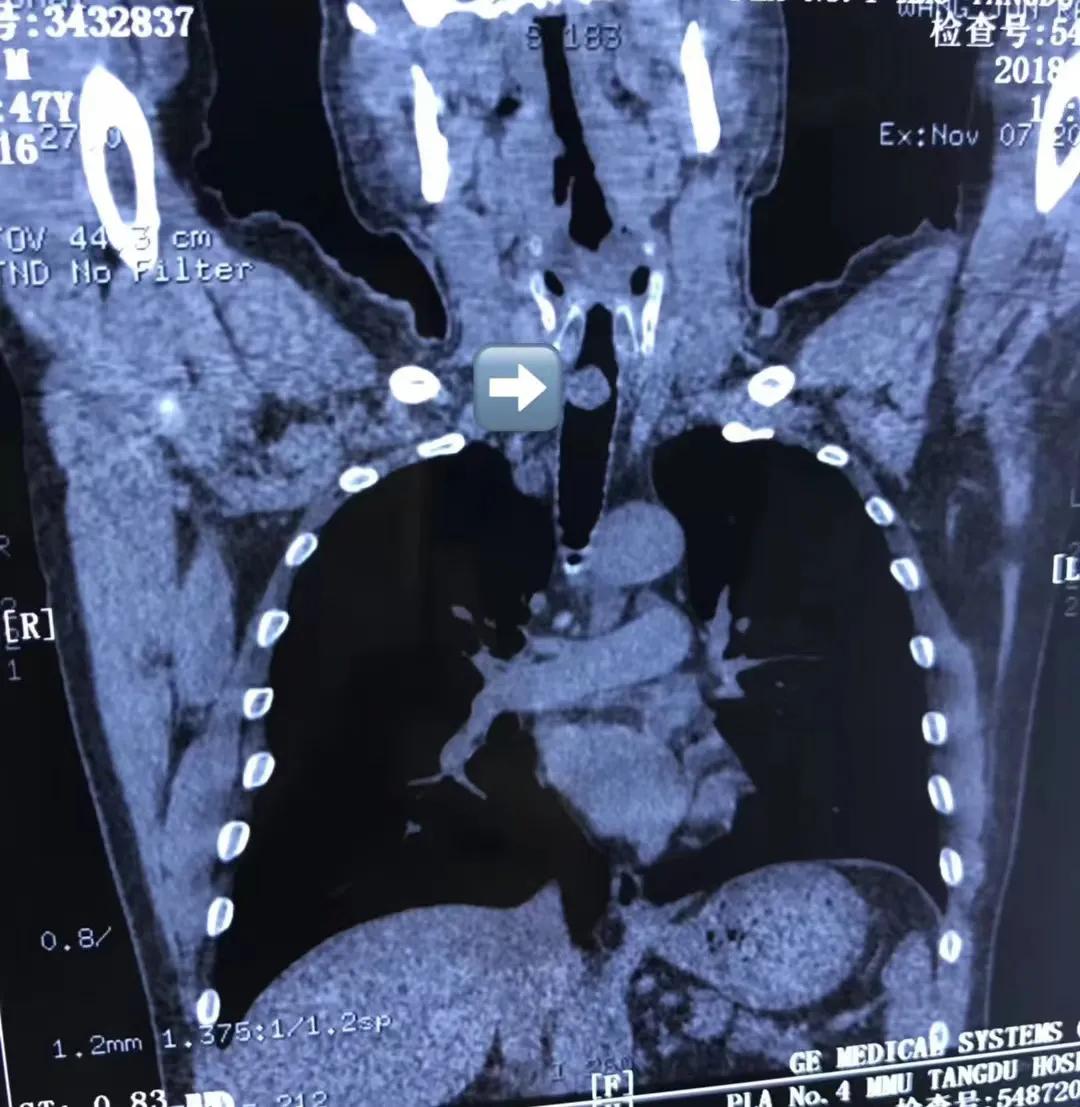

入院急救时,几乎无法喘息。听诊两肺干净,喘息声音似乎出自于喉部。后经胸部CT证实,患者的肺部的确没有问题,顺着CT往上查看,最终找到了症结所在——气管上段可见新生物阻塞管腔,长度约3cm,狭窄约60%。呼吸与危重症医学科顾兴主任介绍,气管是大气道,人体借助上呼吸道、气管和双侧支气管与左、右肺相连,人体正常气管是1.5~2cm左右,而患者气管狭窄最狭窄部位却仅有4mm! 几乎将气管完全堵塞,人活一口气,当双肺的入口通道---气管被阻塞后,人的呼吸困难可想而知。

术前,介入团队为王先生完善了相关的检查,心脏、肝肾功能的手术评估,排除禁忌症,以及颈部CT,精准测量狭窄部位的高度、深度,最狭窄段的距离,狭窄的长度等等。呼吸介入团队特邀请麻醉科、影像科等科室开展了多学科联合会诊,预判术中出血、撕裂可能,制定多个手术方案,以应对术中突发问题。